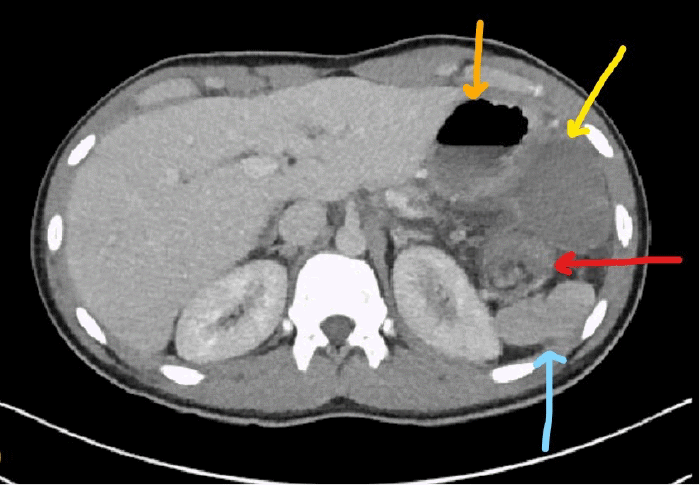

An abnormal twisting configuration, known as the "swirl sign," was observed in the left-upper to mid-abdominal mesentery, leading to the presence of a very large accessory spleen measuring 14 × 5 × 6 cm. This accessory spleen was partially vascularized and situated adjacent to the gastric wall, with its superior aspect being nonvascular (Figure 2). Notably, prominent inflammatory stranding surrounding the mesentery was also identified. The patient was determined to have a large accessory spleen with volvulus, resulting in an infarction or injury (Figure 3).

Stomach (orange arrow), accessory spleen (yellow arrow), "swirl sign" (red arrow), and native spleen (blue arrow)

Figure 3. Accessory Spleen Demonstrating Infarcted and Non-infarcted Tissue. Published with Permission